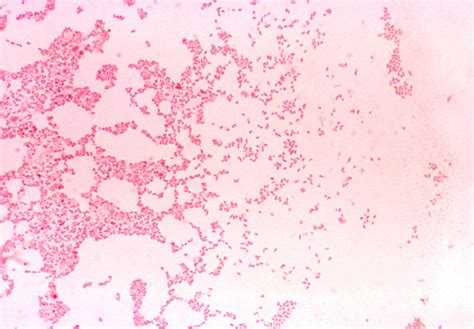

Gram Negative Coccobacilli

Gram Negative Coccobacilli are a group of bacteria that stain negatively in the Gram staining procedure. This staining technique is a fundamental method in microbiology used to differentiate bacteria based on their cell wall characteristics. Gram-negative bacteria have a thin peptidoglycan layer and an outer membrane containing lipopolysaccharides, which contribute to their unique staining properties.

Coccobacilli are bacteria that have a shape intermediate between cocci (spherical) and bacilli (rod-shaped). This morphological feature makes them distinct from other bacterial forms and is an important characteristic for identification purposes.

Gram Staining: The Gram stain is the initial step in identifying Gram Negative Coccobacilli. The characteristic staining pattern helps differentiate these bacteria from other types.